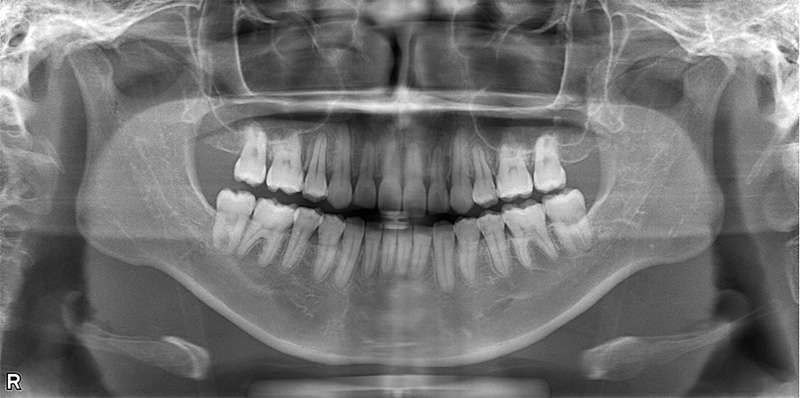

57歳女性

治療前